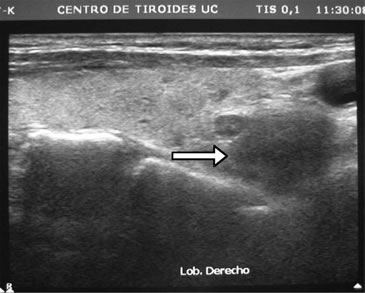

Desde el punto de vista bioquímico sus controles en los últimos 10 años mostraban normalidad de la calcemia y fosfemia. A los 76 años es estudiada en nuestro servicio donde se constata hiperparatiroidismo secundario de doble etiología: hipovitaminosis D e hipercalciuria renal. Sus exámenes de sangre, sin mediar tratamiento, eran: Ca: 9,3 mg/dL; P: 3,5 mg/dL; albúmina: 4,4 g/dL; fosfatasas alcalinas: 78 U/L; PTH: 90,9 pg/mL (VN: 15-65 pg/mL); 25OHD: 10 ng/mL (VN: 20-40ng/ml) y creatinina normal. En orina: Ca: 326 mg/24h; creatinina: 0,92g/24h; Ca/Creat: 0,35. La paciente había sido tratada con dosis bajas de levotiroxina (50 ug/d) y controlada con ecografías cervicales debido a hipotiroidismo subclínico (TSH: 7,1 uUI/mL) detectado a los 69 años, con varios nódulos tiroideos en ambos lóbulos de características coloideas y estables. El mayor de ellos estaba en el polo inferior del lóbulo derecho y medía 8 x 6,5 x 4 mm. Repetido el estudio 1 mes después con un ecógrafo de 12,5 MHz se agrega a la descripción anterior, bajo maniobra de compresión zonal, un nódulo ovalado, de 7,8 mm de diámetro mayor, hipoecogénico, homogéneo, de limites difusos, ubicado en posición retrotiroidea del polo inferior derecho, visualizándose al doppler vasos de entrada y salida con abundante circulación intranodal (Figura 2a). Se efectuó punción con aguja fina (PAF) obteniendo buena muestra, pero el procedimiento se complica con sangramiento (Figura 2b). El informe histopatológico certifica células paratiroideas de aspecto normal,lo que se corrobora con la positividad de la tinción inmunohistoquímica con anticuerpos monoclonales para PTH, según técnica S-ABC.

Comentario especial merece el estudio ecográfico de las glándulas paratiroideas, en que la técnica no corresponde a la simple extensión de la usada en el diagnóstico de nódulo tiroideo. Para el estudio ecográfico de las glándulas paratiroides es importante ejercer presión con el transductor sobre los tejidos cervicales, para acercar las glándulas paratiroides al foco del transductor, y así poder obtener imágenes de ellas. De lo contrario, la distancia habitual entre transductor y glándula paratiroidea es tal que disminuye notoriamente la sensibilidad de la búsqueda. Otra forma de optimizar la visión ecográfica es agregando un baño de agua, dado que la conducción acústica es óptima en medio líquido; en nuestro caso, el hematoma derivado de la PAF generó espontáneamente un medio acuoso, lográndose una clara visualización de la glándula paratiroides, desapercibida en los exámenes anteriores (Figura 2b).